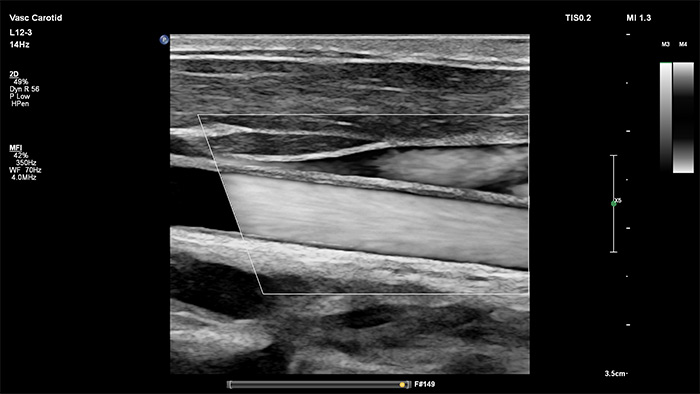

O processamento de imagens da Philips da nova geração eleva a imagem vascular a novos níveis, proporcionando uma delineação soberba de interfaces de vasos e uma melhor conspicuidade de textura de placas. Ao reduzir os artefactos e o "nevoeiro" dos vasos, o XPRES Pro aumenta a confiança no diagnóstico durante a imagem vascular dos pacientes, incluindo os que são tecnicamente difíceis.

Learn more about the Philips L12-3 broadband linear array transducer in the specification table below.